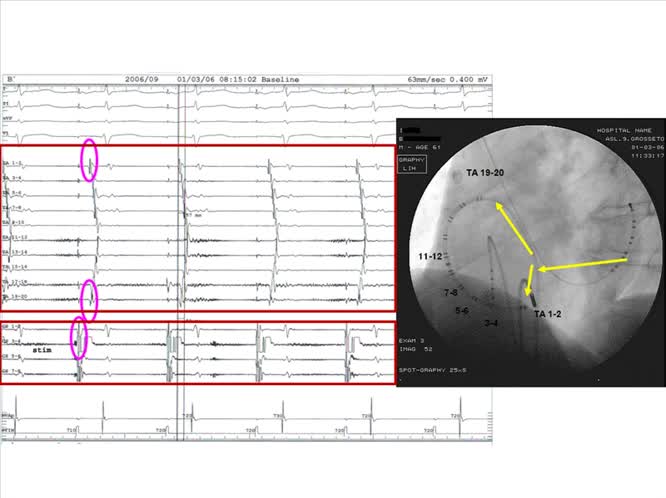

Ablazione del Flutter Atriale Validazione del Risultato

: Cuore Maremma

: L. Addonisio |

: 01 ottobre, 2010 |

: ITA |